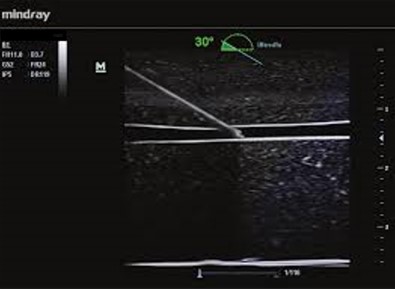

iNeedle - Vylepšenie vizualizácie pomocou ihly iNeedle

iNeedle (kontrastná vizualizácia punkčnej ihly)

iNeedle: Kontrastné zobrazenie bioptickej ihly.

iNeedle: Kontrastné zobrazenie bioptickej ihly.

iNeedle - Vylepšenie vizualizácie pomocou ihly iNeedle